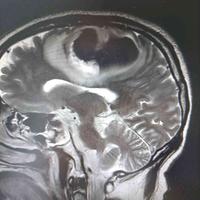

77岁老年男性,突发昏迷24小时入院。既

77岁老年男性,突发昏迷24小时入院。既往无高血压病史。近半年右前臂背侧常有皮下淤血斑。...

由 medjpg 发表于 2026-03-24 22:32